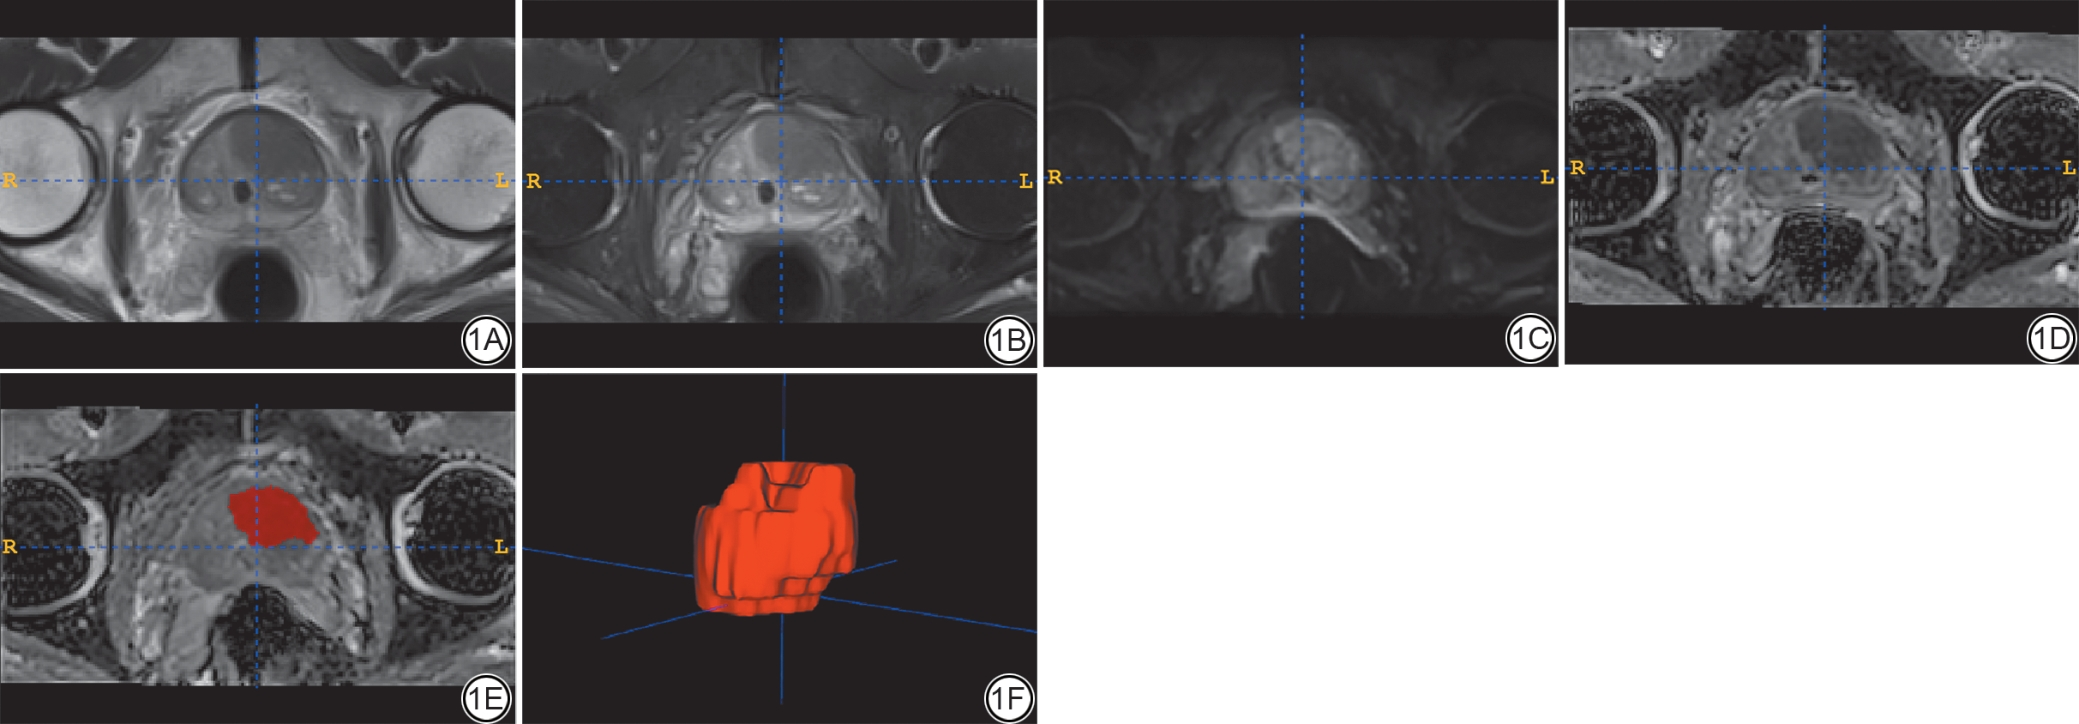

本研究图像分割采用软件ITK-SNAP(3.8.0版)完成。放射科医师A(有5年前列腺MRI诊断经验的住院医师)在轴向T2WI和ZOOMit-DWI上独立盲法勾画感兴趣区(region of interest, ROI)(图1)。然后将DWI ROI复制到相应的表观扩散系数(apparent diffusion coefficient, ADC)图上。为便于解剖学参考,我们参考了穿刺和/或术后的病理报告。勾画时包括整个病变而不超出其边缘,同时尽可能避免尿道、钙化区域、出血和邻近结构,如膀胱、血管和神经静脉丛。所有ROI均接受了高年资医师B(有10年以上MRI诊断经验的副主任医师)和医师C(有15年以上MRI诊断经验的主任医师)的审查和调整从而达成共识,以最大限度地减少周围组织对图像的影响。

图1  男,69 岁,前列腺癌患者,红色区域为ROI。1A:T2WI 图像;1B:T2WI-FS 图像;1C:ZOOMit-DWI(b=1000 s/mm2)图像;1D:ZOOMit-ADC图像;1E:基于ZOOMit-ADC 的二维感ROI 图像;1F:三维ROI 图像。ROI:感兴趣区;FS:脂肪抑制;DWI:扩散加权成像;ADC:表观扩散系数。

Fig. 1  Male, 69-year-old, a prostate cancer patient, red represents the ROI. 1A: T2WI image; 1B: T2WI-FS image; 1C: ZOOMit-DWI (b = 1000 s/mm2) image; 1D: ZOOMit-ADC image; 1E: Two-dimensional ROI image based on ZOOMit-ADC; 1F: Three-dimensional ROI image. ROI: region of interest; FS: fat suppression; DWI: diffusion weighted imaging; ADC: apparent diffusion coefficient.